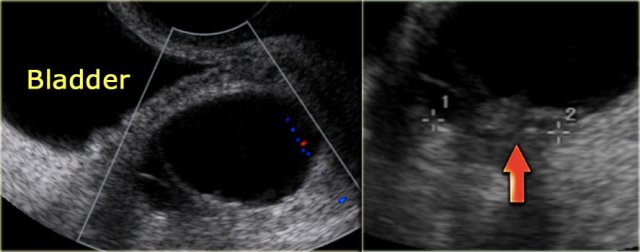

The transvaginal ultrasound images show a small complex ovarian cyst with wall vascularity on power Doppler analysis.

The characteristic circular Doppler appearance is called the 'ring of fire'.

Note, there is good through-transmission and no internal vascularity, consistent with a, partially involuted, corpus luteum cyst.

Another case with the typical the 'ring of fire' on ultrasound.

At pathologic examination the collapsed bloody cyst can be clearly seen.

Corpus luteum cyst at MRI: an axial T2-weighted image demonstrating an involuting corpus luteum cyst (arrow).

This is a normal finding.

The right ovary is also normal.